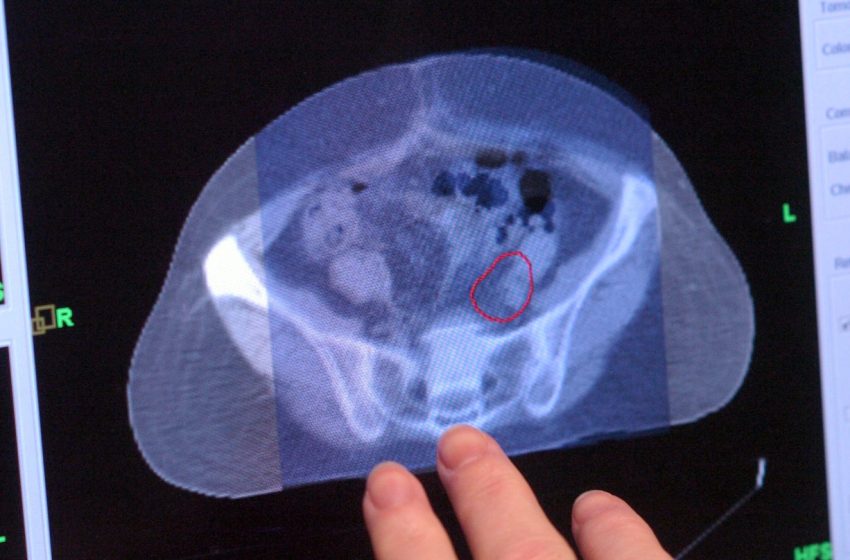

Colorectal cancer occurs in the colon or the rectum, which together make up the large intestine and are part of the digestive system.